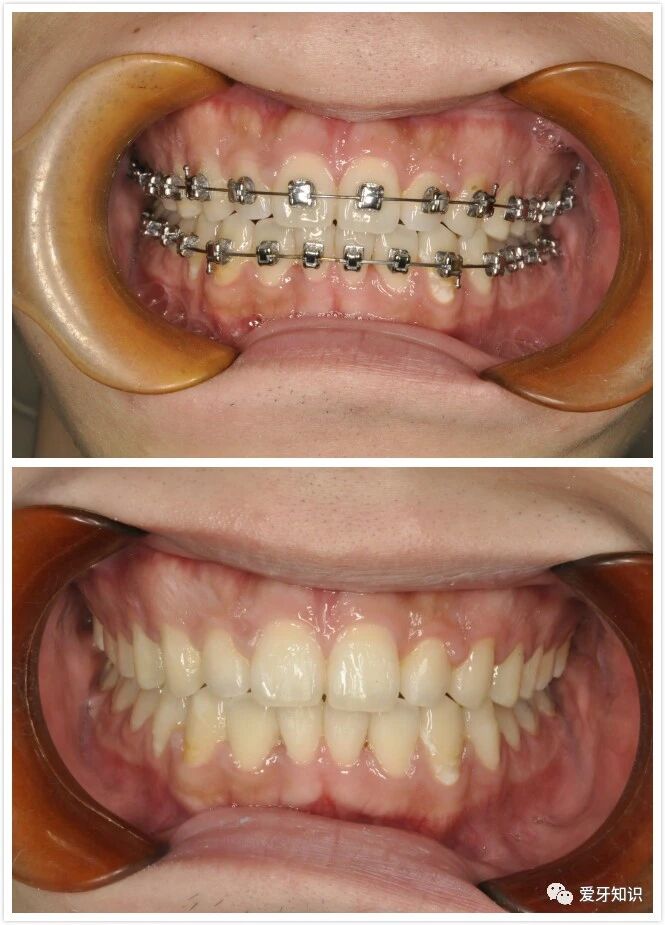

带牙套

分牙完成后就可以直接上牙套了。(戴牙套初期有点磨嘴,第一个星期可能会有牙周酸软感,之后不适症状将会消失。如果有口腔溃疡,可以晚上睡觉前喷桂林西瓜霜,补充点维生素B、锌等。)

摘牙套

最激动人心的时刻到了!为了更加完美,你可以去洗个牙或者做个美白。让自己更加自信,神采飞扬。